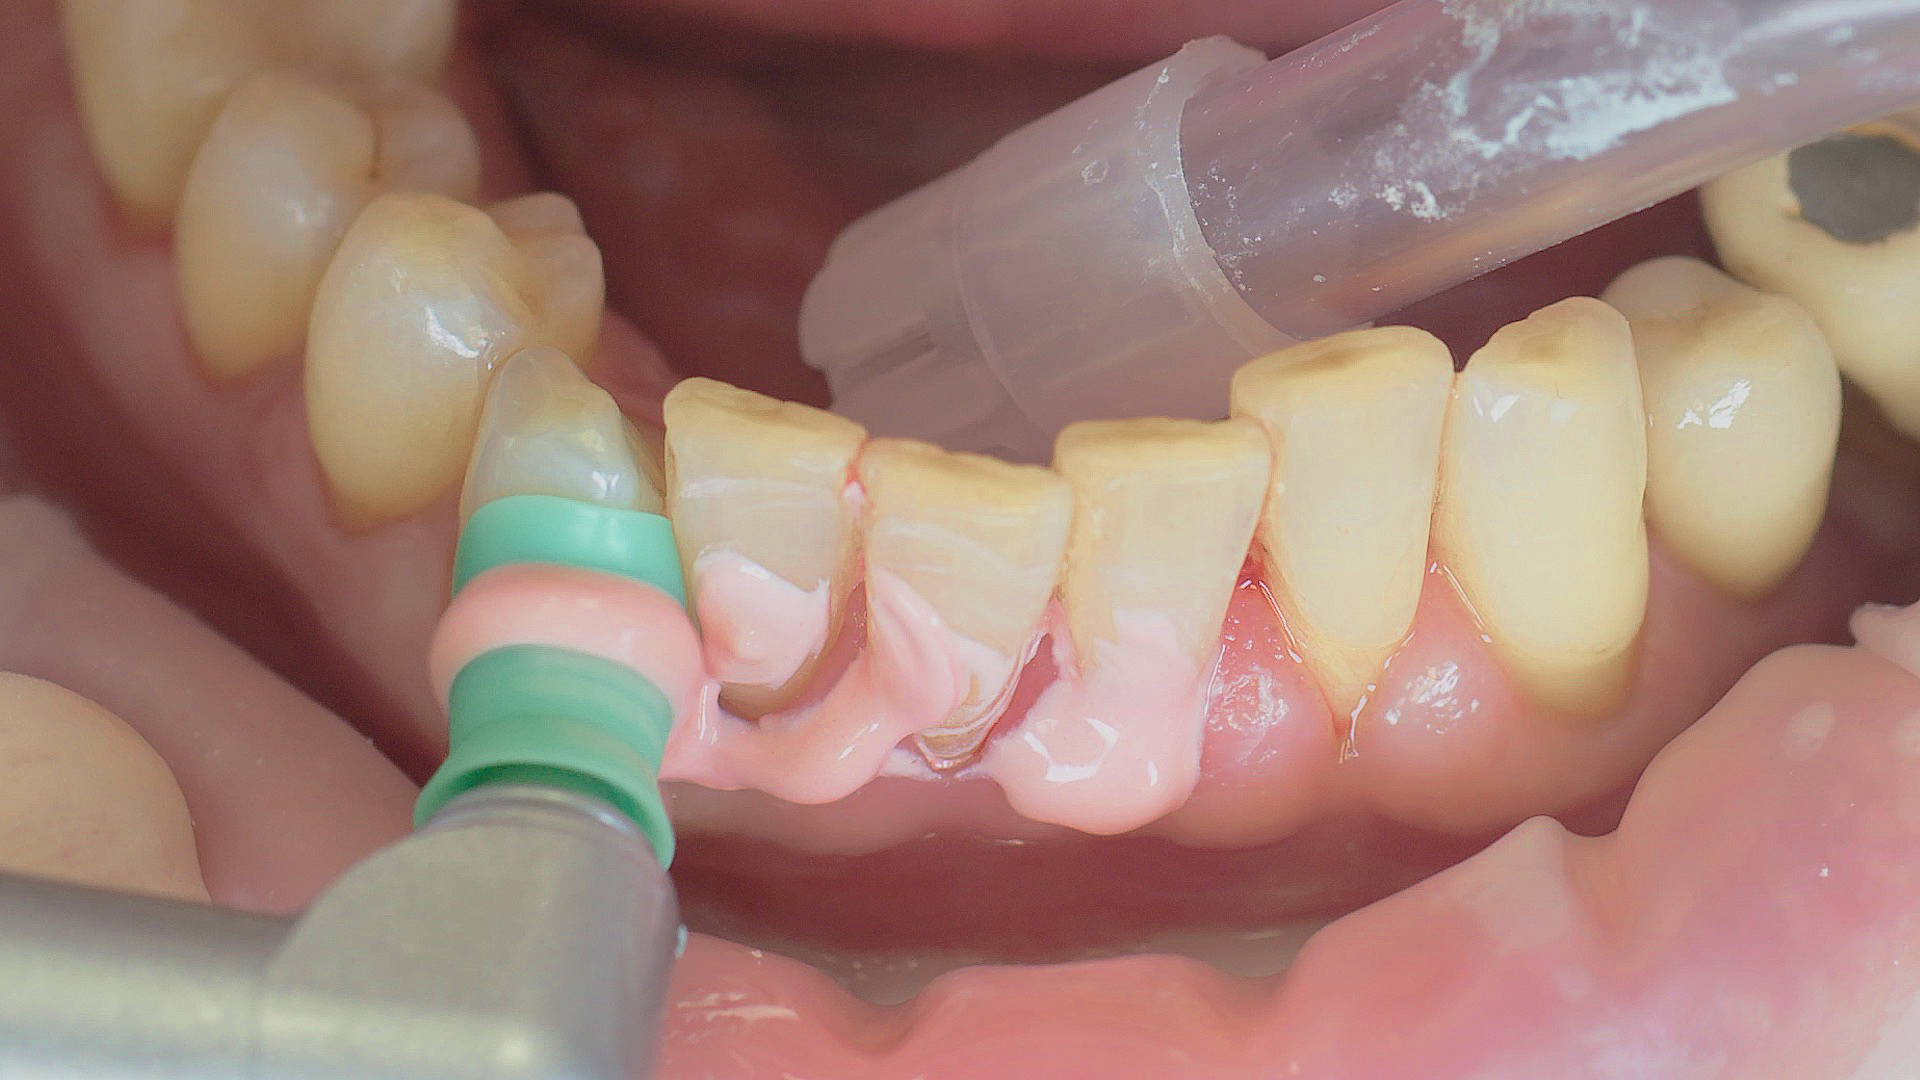

Removal of subgingival coatings (debridement) is carried out using sonic or ultrasonic devices and special periodontal tips as initial periodontal treatment (Fig. 3). Manual instruments can also be used. Further surgical and/or regenerative measures may be necessary, depending on the situation.